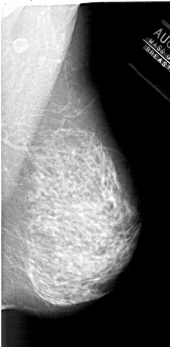

A_1878_1.RIGHT_CC

RIGHT_CC LINES 5971 PIXELS_PER_LINE 3091 BITS_PER_PIXEL 12 RESOLUTION 43.5 NON_OVERLAY